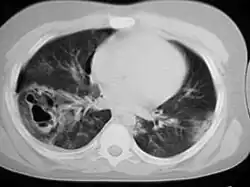

Computed tomography

Computed tomography (CT scanning) is a more sensitive test for pulmonary contusion,[8][38] and it can identify abdominal, chest, or other injuries that accompany the contusion.[43] In one study, chest X-ray detected pulmonary contusions in 16.3% of people with serious blunt trauma, while CT detected them in 31.2% of the same people.[50] Unlike X-ray, CT scanning can detect the contusion almost immediately after the injury.[48] However, in both X-ray and CT a contusion may become more visible over the first 24–48 hours after trauma as bleeding and edema into lung tissues progress.[51] CT scanning also helps determine the size of a contusion, which is useful in determining whether a patient needs mechanical ventilation; a larger volume of contused lung on CT scan is associated with an increased likelihood that ventilation will be needed.[48] CT scans also help differentiate between contusion and pulmonary hematoma, which may be difficult to tell apart otherwise.[52] However, pulmonary contusions that are visible on CT but not chest X-ray are usually not severe enough to affect outcome or treatment.[42]